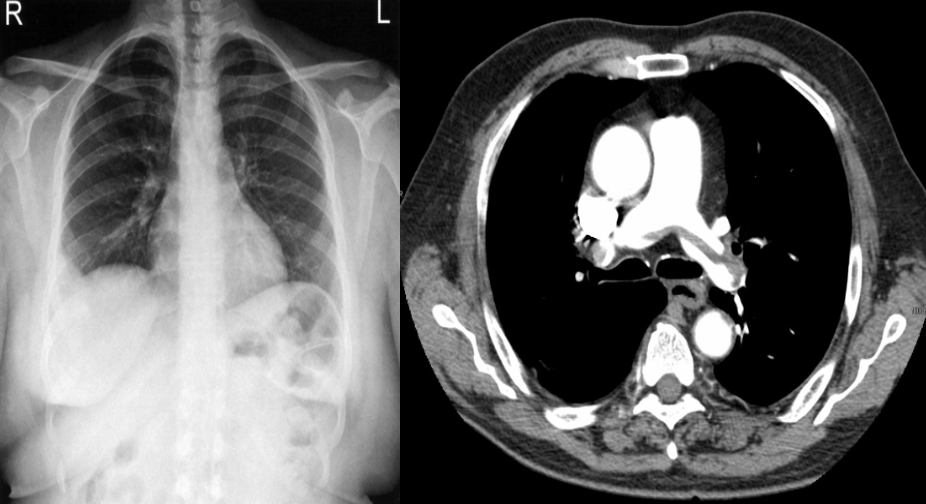

in Chest X-ray - PA View:

A peripheral opacity (Hampton hump; obscures the adjacent margin of the right hemidiaphragm. The appearance is often wedge-shaped.

Hampton hump: a wedge-shaped opacity in the peripheral lung with its base at the thoracic wall; caused by pulmonary infarction and not specific for PE.

Westermark sign: an area of lung parenchyma lucency caused by oligemia secondary to occlusion of blood flow.

Fleischner sign: a prominent pulmonary artery caused by vessel distention due to a large pulmonary embolus (common in massive PE)

CT chest (with contrast; axial plane)

A large embolism is seen, with extension across the bifurcation of the pulmonary trunk into the right and left pulmonary arteries. Straddling of the pulmonary trunk bifurcation by pulmonary embolism is sometimes referred to as saddle embolism.